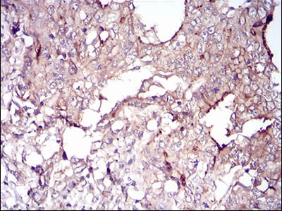

IHC    1/200 - 1/1000